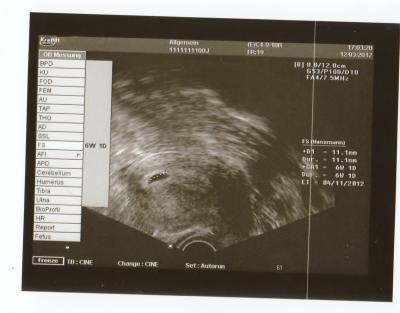

Eine leere Fruchthöhle kann bei einer Ultraschalluntersuchung festgestellt werden, wenn sich in der Gebärmutter keine Embryonalanlagen entwickelt haben. Dies wird oft als Windei bezeichnet. Es handelt sich dabei um eine Art Fehlentwicklung, bei der sich nur die äußere Zellschicht der Keimblase gebildet hat, jedoch kein Embryo vorhanden ist.

In den meisten Fällen deutet eine leere Fruchthöhle auf eine nicht intakte Schwangerschaft hin und bedeutet, dass die Schwangerschaft vorzeitig beendet werden muss. Es kann jedoch auch vorkommen, dass sich der Embryo noch nicht ausreichend entwickelt hat und daher noch nicht sichtbar ist. In solchen Fällen wird häufig zu einem späteren Zeitpunkt eine erneute Ultraschalluntersuchung durchgeführt, um das weitere Vorgehen zu bestimmen.

Leere Fruchthöhle in der Ultraschalluntersuchung: Was bedeutet das für die Schwangerschaft?

Eine leere Fruchthöhle in der Ultraschalluntersuchung kann ein Anzeichen dafür sein, dass die Schwangerschaft nicht wie erwartet verläuft. Wenn bei einem positiven Schwangerschaftstest keine embryonalen Strukturen in der Fruchthöhle sichtbar sind, spricht man von einem „Windei“. Dabei hat sich zwar die äußere Zellschicht gebildet, aber es fehlen die Embryonalanlagen. In solchen Fällen kann sich die Schwangerschaft nicht weiterentwickeln.